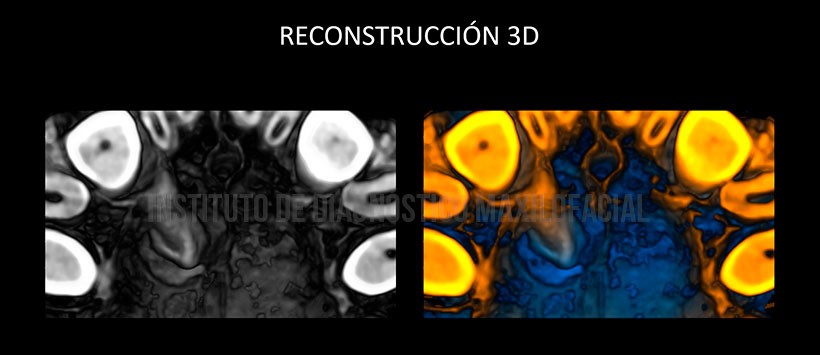

En las reconstrucciones 3D se muestra de manera ilustrativa la pieza dentaria supernumeraria previamente descrita así como su localización y repercusión con las estructuras adyacentes. (Figura 4, Figura 5 y Figura 6)

- Pieza dentaria supernumeraria retenida con aumento del saco pericoronario.